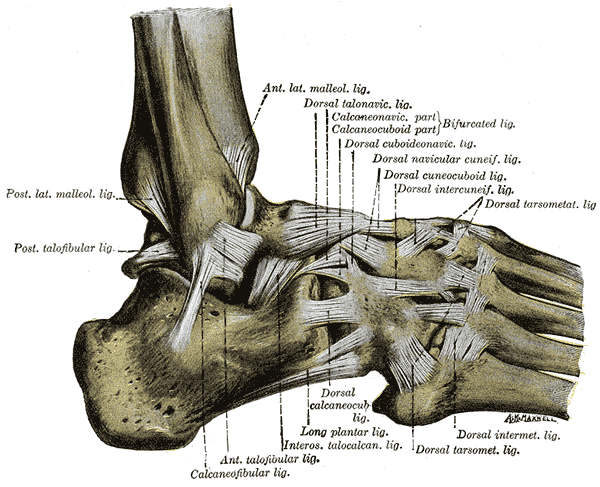

首先,让我们来谈谈解剖学。 踝关节由两个不同的关节组成:

- "(《世界人权宣言》) 距骨关节 这是一个铰链关节,允许在矢状面上进行两个主要运动: 跖屈 和 外翻

- 踝关节也被认为是铰链关节,但其旋转轴是斜向的。 在这个关节上可能出现的动作有 转位 (跖屈、内收和上翻的组合)和 转位 (背屈、外展和前倾的组合)。

请注意: 在美国的术语中,内翻被称为上翻,外翻被称为前翻。